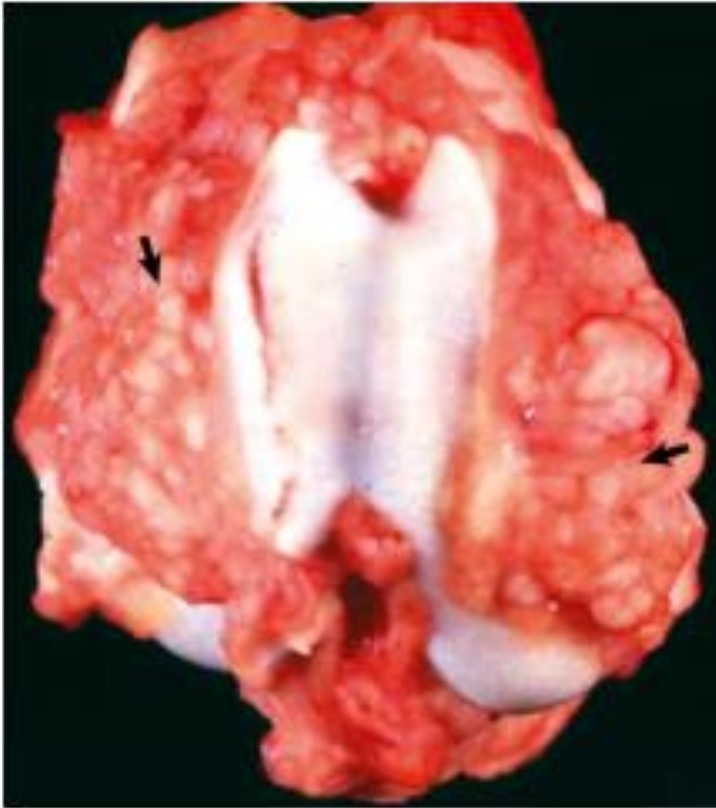

What is affecting this feline rib? note the multilobulated white to gray mass with invasive destruction and loss of normal bone architecture.

chondrosarcoma